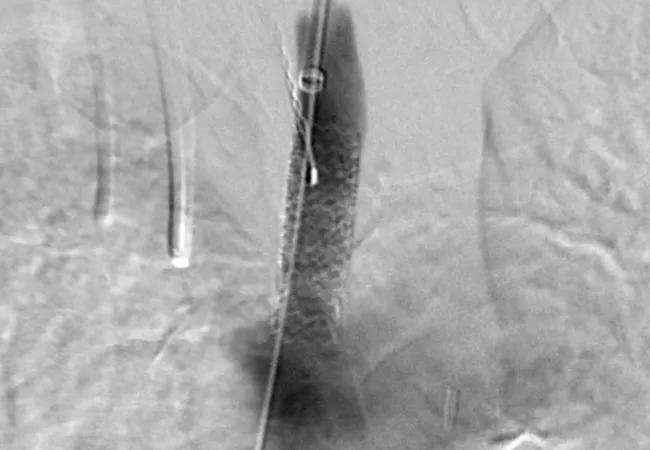

20-HVI-1868665-carotid-artery-stenting

Current evidence supports Centers for Medicare & Medicaid Services (CMS) reimbursement for endovascular treatment of asymptomatic carotid artery stenosis in appropriate patients if it can be regulated through standardized training, data collection and reporting. So contends a multicenter group of cardiovascular clinicians in a recent review in the Journal of the American College of Cardiology featured as a “JACC review topic of the week.”